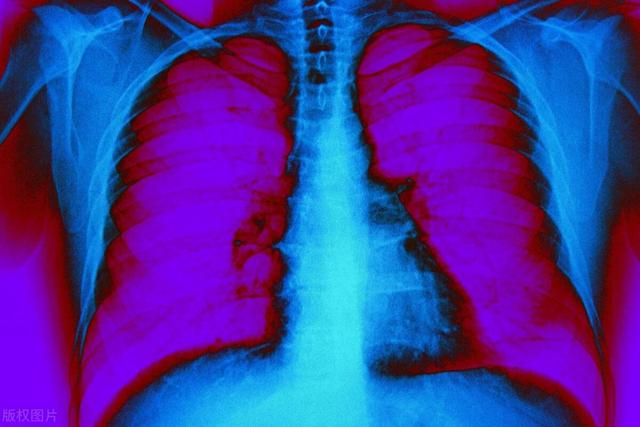

【医生回答】肺癌是全球范围内最常见的癌症之一 , 它常常在早期不容易察觉 。 然而 , 一些研究表明 , 睡眠中出现的一些异常可能是肺癌等癌症的预警信号 。 本文将深入探讨睡觉中出现的四种异常情况 , 可能与肺癌发生相关 , 并提供关于如何及早发现和处理这些信号的建议 。

肺癌是一种严重的恶性肿瘤 , 它通常起源于支气管或肺组织 。 这种病症的危害在于早期常常没有明显的症状 , 让许多患者在确诊时已经到了晚期 , 这时治疗效果往往不尽人意 。 因此 , 早期发现肺癌的重要性不可低估 。

肺癌在早期阶段可能表现为轻微的症状 , 比如咳嗽、轻微的呼吸困难或胸痛 , 这些症状很容易被忽略或误认为是普通的呼吸道感染 。 随着肿瘤的增长 , 可能会出现咳嗽加重、咳出血痰、体重下降、乏力等症状 。 但这些症状在其他疾病中也常见 , 因此容易被忽视 。 一旦肺癌扩散到其他部位 , 可能出现更严重的症状 , 如胸痛、气促、骨痛、头痛等 , 这时候治疗难度和风险都会大大增加 。